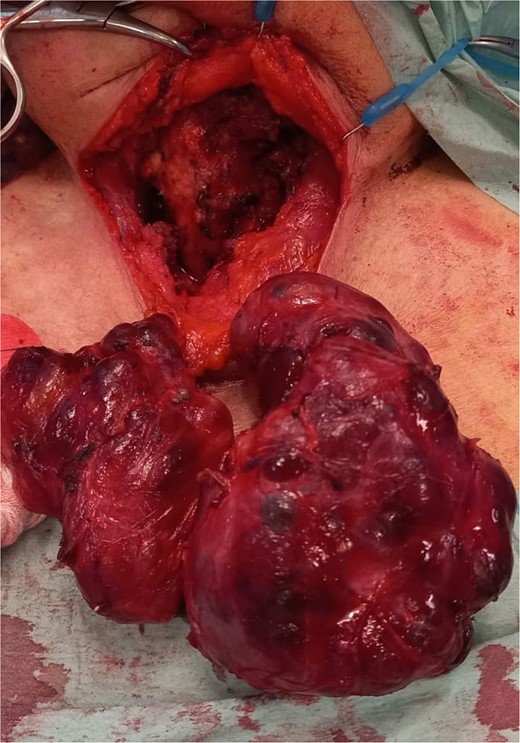

The patient was admitted to the Intensive Care Unit (ICU). A positive Pemberton sign was found on physical examination (Fig. 3). The thyroid hormones were normal with a slightly decreased TSH. The case was discussed in a multidisciplinary meeting and surgical treatment was decided. On the fourth day of admission, the patient underwent a total thyroidectomy (Fig. 4), parathyroid autotransplantation, and tracheostomy. The procedure was uneventful. The histological examination revealed nodular hyperplasia of the thyroid with foci of micropapillary carcinoma (4 mm) in the right lobe. The patient was extubated and discharged from the ICU on the second postoperative day. She initiated a physical and speech therapy programme. The follow-up nasopharyngoscopies showed a slow but progressive improvement of the laryngeal oedema, which required a longer admission. After a few unsuccessful attempts, she was finally decannulated on the 39th postoperative day and was soon discharged home. She progressed well and two and a half years after the surgery she is asymptomatic, with no dysphonia or respiratory distress. She has a subclinical hyperthyroidism that has been monitored in annual follow-up appointments.